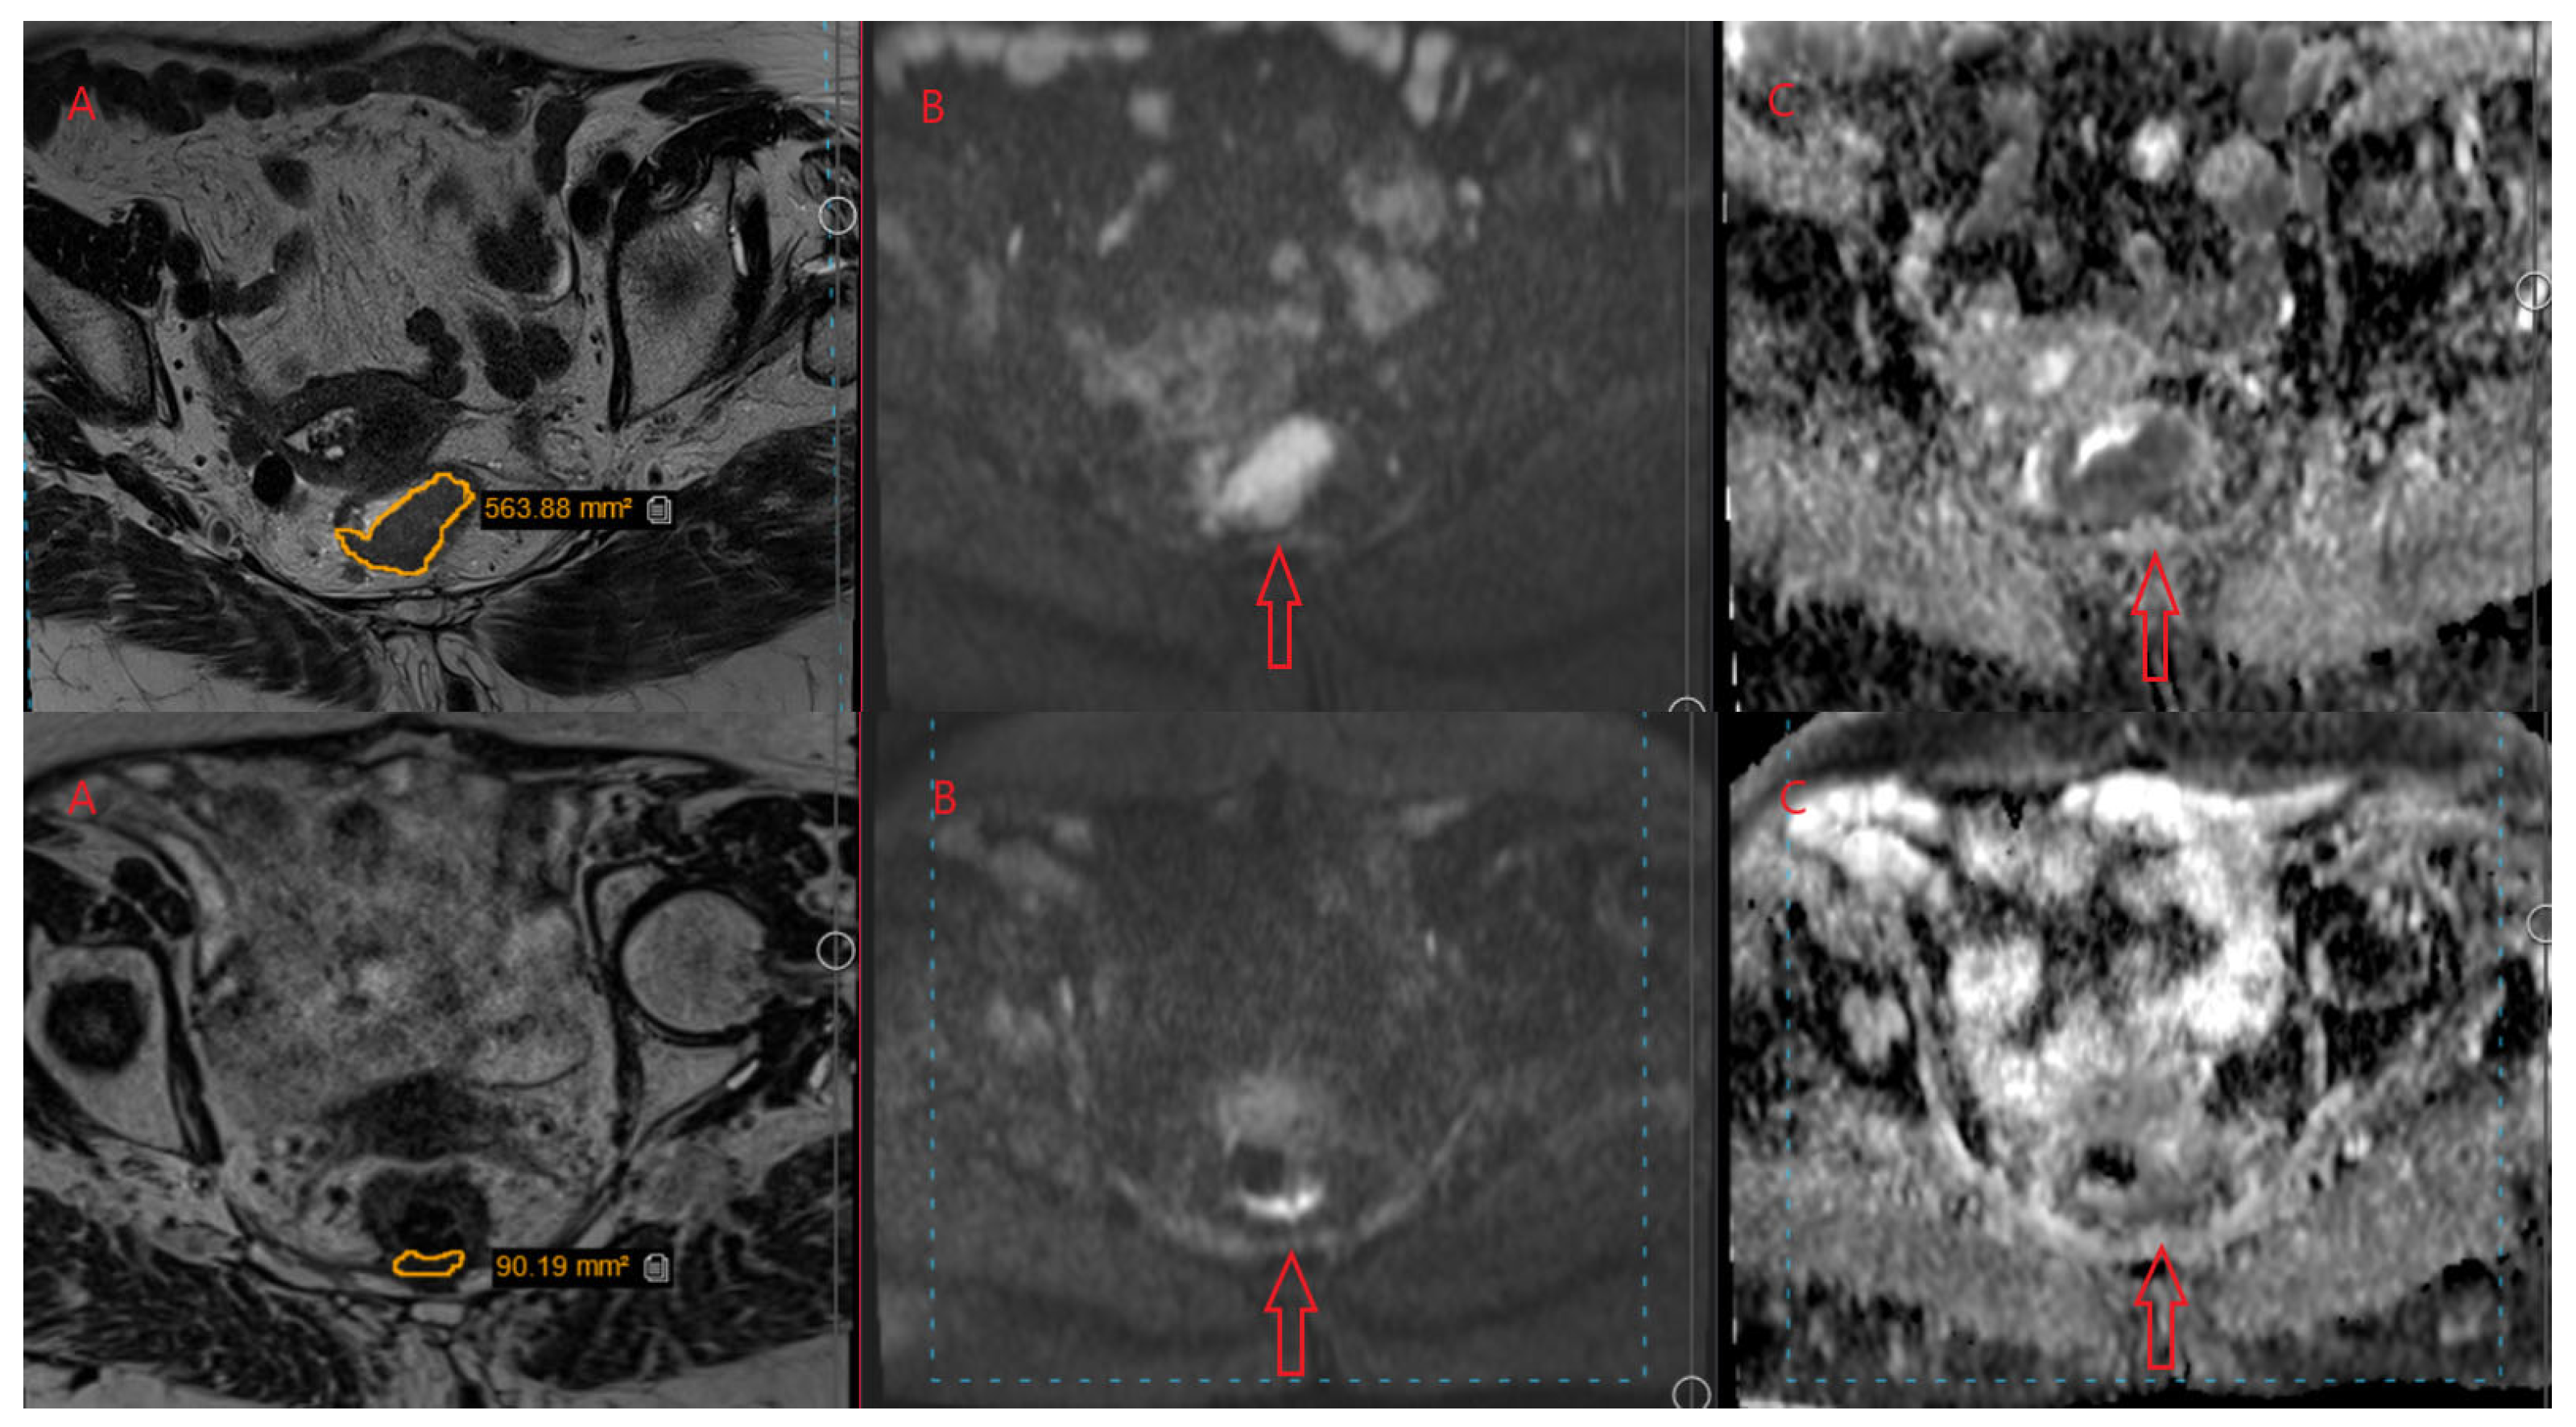

2.3. MR Volumetry and Tumor Regression Grade (mrTRG and pTRG)